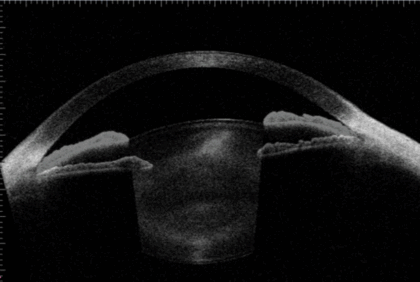

隅角が非常に狭く、眼圧が非常に上昇し緑内障発作となっている状態

白内障手術を行い、隅角が広がった状態

手術前後の画像を重ね合わせると、隅角が広がっていることがよくわかります